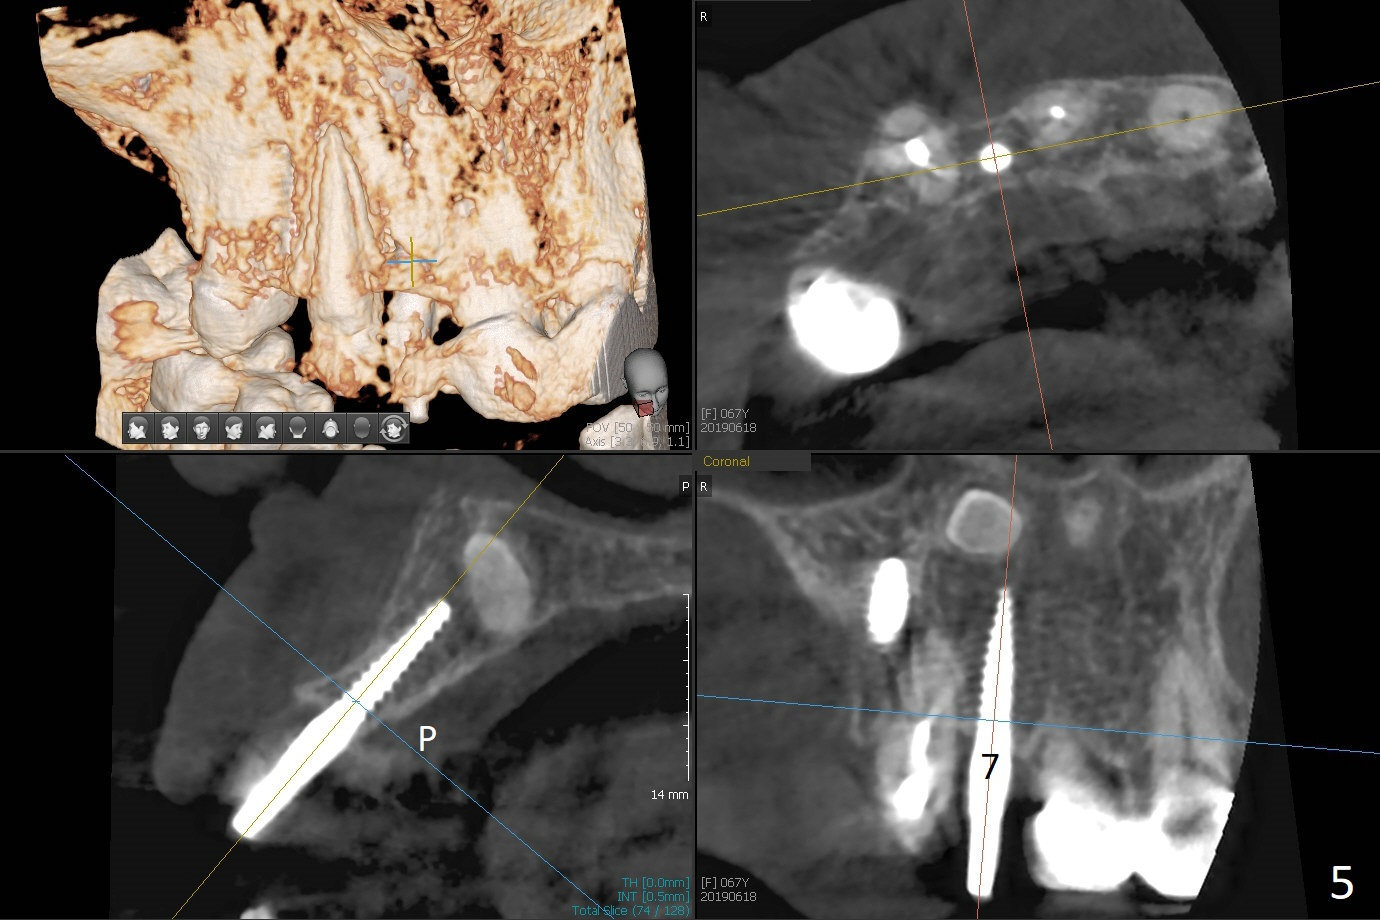

Two of 5x8.5 mm implants are placed at #2 and 3 with sinus lift using water ballooning technique; to avoid invading the neighboring root tips, an intraop PA is taken with a 2.2x11.5 mm drill at #5 (Fig.1). When a 2.5x11.5 mm 1-piece implant is placed at #7, there is 2.4 mm clearance from the impacted tooth (Fig.2). Following 1 mm deeper placement of the 1-piece implant, CT is taken to make sure that the threads are completely covered palatally (Fig.5 P). Interesting is that the sinus membrane is thickened at #2 and 3 (Fig.3 M), as compared to the clear sinus before surgery (Fig.3'). Bone graft is limited in the sinus (Fig.3 arrowheads). The implant at #5 (3.5x11.5 mm) is precisely placed subcrest bucco(B)-palatally (Fig.4). Since the limited field viewed CT does not cover the implant at #2 (Fig.3), immediate postop PA is taken (Fig.6). In fact all of the implants are placed subcrestal, as shown by intraoral X-ray 4 months postop (Fig.7-9). The abutments at #2, 3 and 5 are retorqued (30 Ncm) after crowns' try in and adjustment (Fig.10,11). There is a vertical gap between the implant and abutment at #2 (Fig.11 ^) and a horizontal one at #5 (<). There is apparently no bone loss 1 year 5 months post cementation (Fig.12).